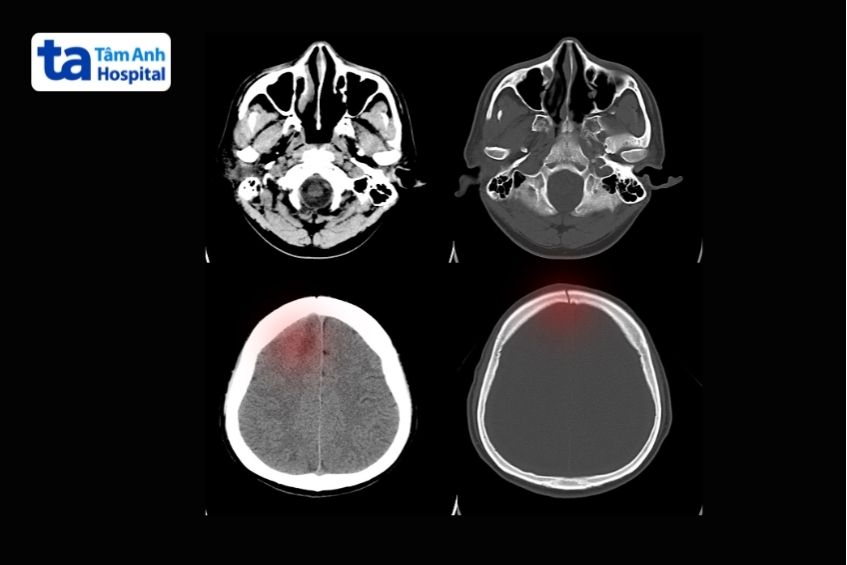

Tụ máu ngoài màng cứng (epidural hematoma): Biểu hiện dưới dạng vùng tăng tỷ trọng nằm sát mặt trong của xương sọ, hình thấu kính hai mặt lồi. Một mặt áp sát xương, mặt còn lại hướng vào não. Ổ máu tụ thường rõ trong những ngày đầu. Nếu không được phẫu thuật sớm, máu có thể bị dịch hóa, làm hình ảnh trên CT trở nên đồng nhất hoặc giảm tỷ trọng so với mô não. Các ổ nhỏ có thể tự hấp thụ sau một thời gian.

Ảnh chụp CT biểu hiện máu tụ ngoài màng cứng